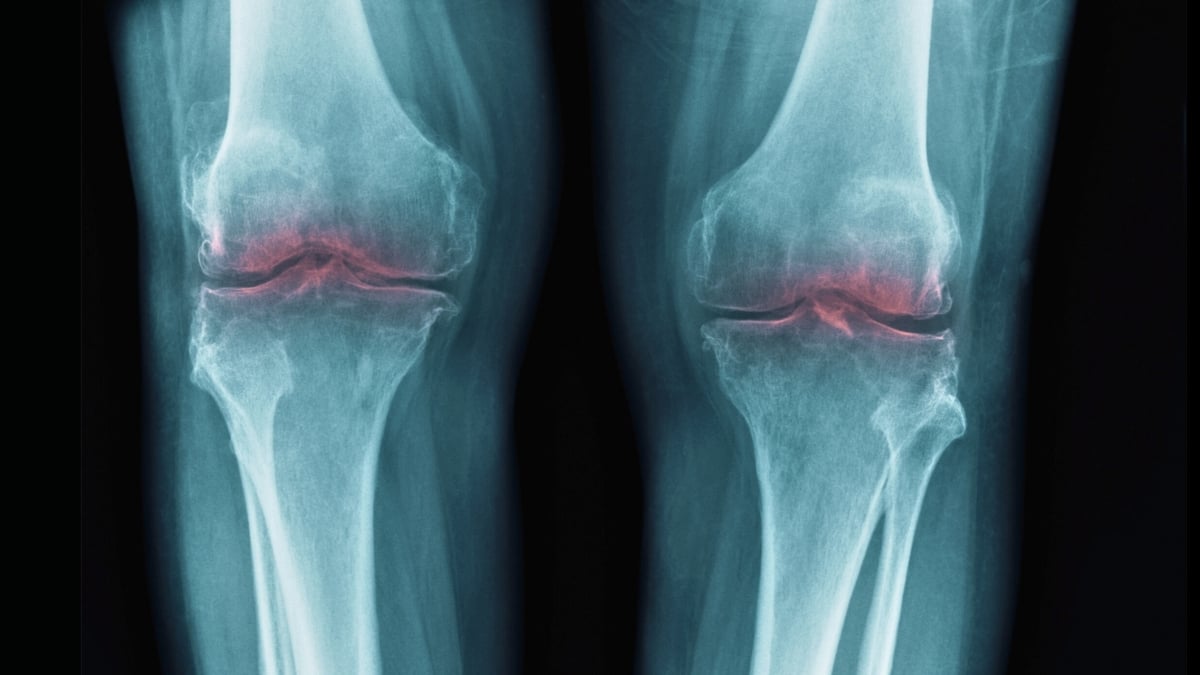

Stanford finds the switch for joint aging: an injection could prevent millions of knee replacements – Sinaptica

Stanford finds the switch for joint aging: an injection could prevent millions of knee replacements – Sinaptica